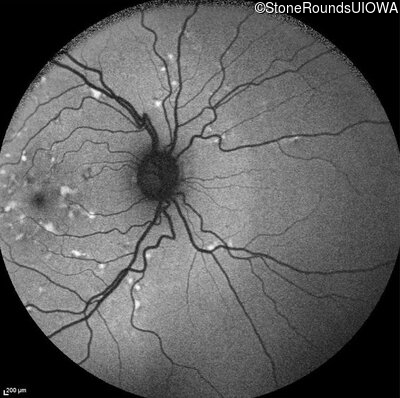

Infrared Fundus Photograph - Left - 20/20 -3

Exemplar